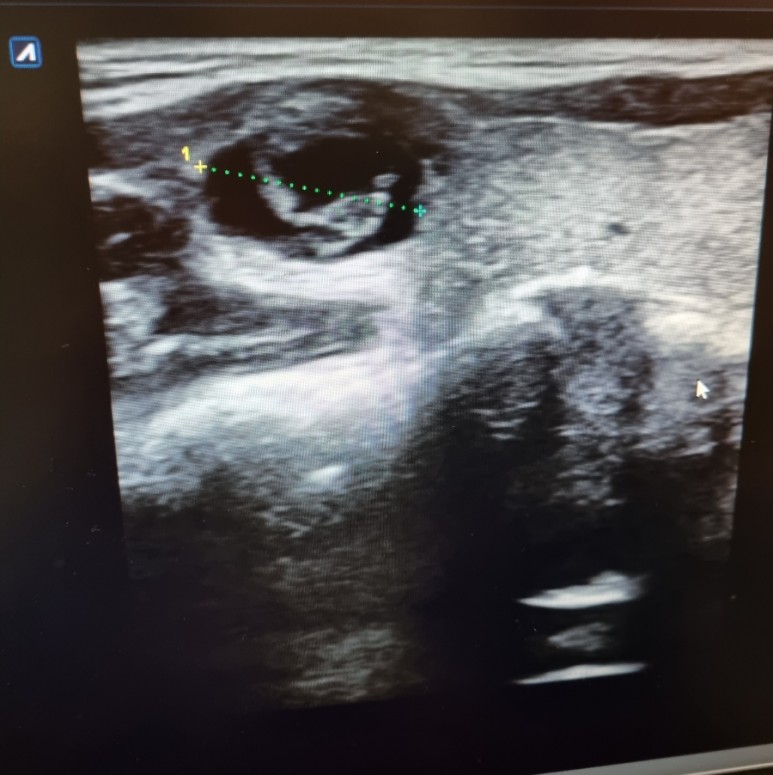

검사 결과 갑상선 결절이 있고 갑상선 맨 윗부분에 위치한

생각보다 사이즈가 컸어 ㅠㅠ 무려 1.5cm ….그동안 어떻게 몰랐을까 하고 의아했다

가로로 길고, 종양의 안쪽은 완전히 지쳐 있는 것, 주변 세포와 경계가 분명한 것 등 종양의 형태는 거의 좋았다.

그런데!! 목 근육 조직과의 경계가 조금 불분명하다면서 조직검사를 하는 것이 좋겠다고 하셨어…(암일 가능성이 있다고..)